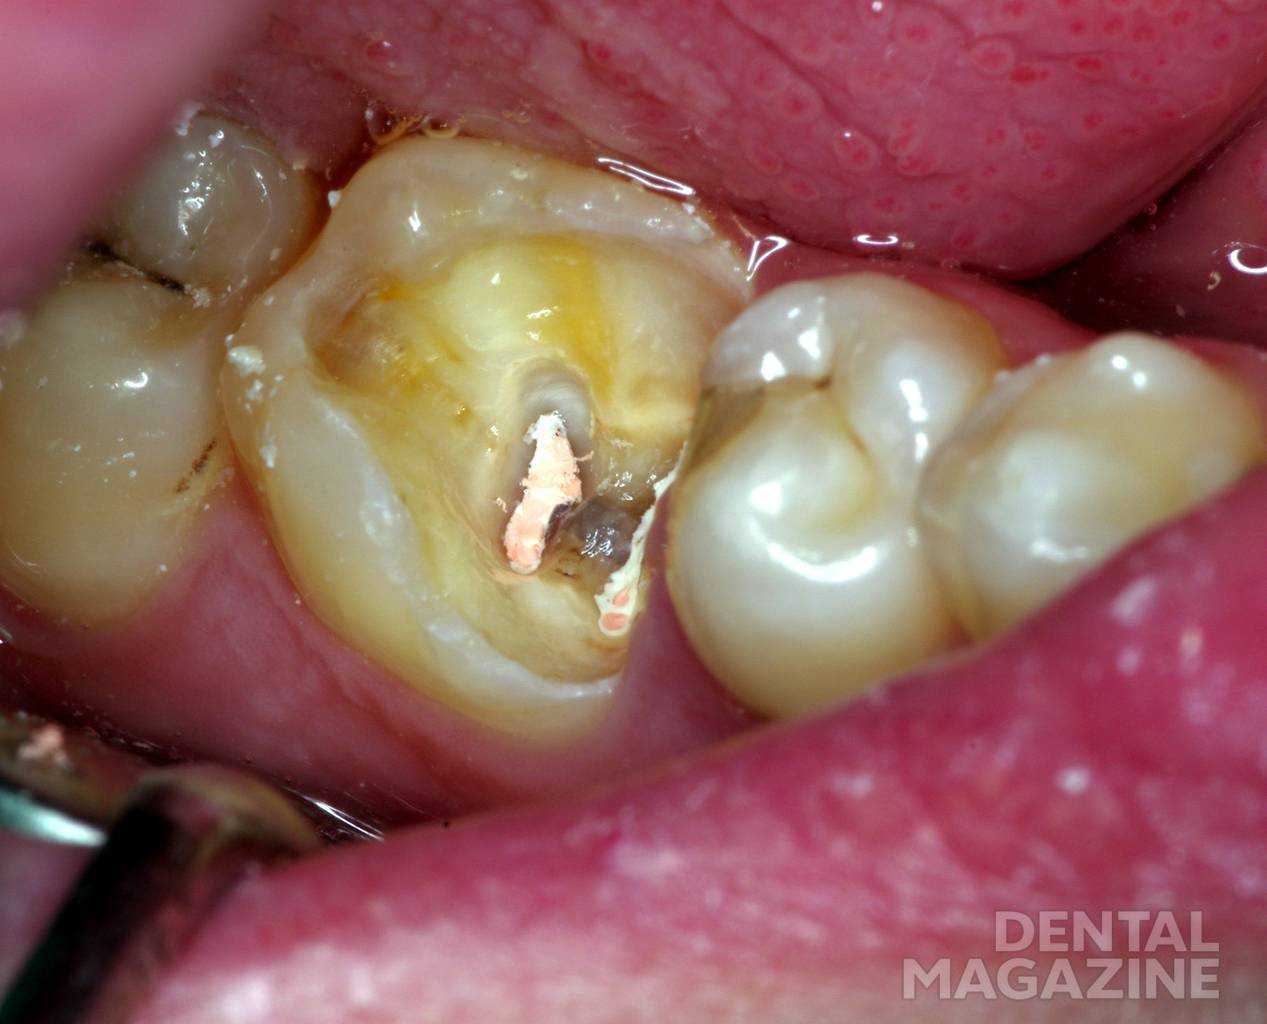

При лечении пульпита ампутационным методом возможно травмирование корневой части пульпы в случае отсутствии адекватного доступа к устьям каналов (рис. 4).

Рис. 4. Гипертрофированная десна препятствует обзору полости.

Излишнее давление на бор или экскаватор вызовет кровотечение из канала вследствие разрыва сосудисто-нервного пучка. Наложение лечебной прокладки над устьем канала под давлением способствует нарушению кровообращения и функционирования корневой пульпы (рис. 5). В любом случае травма корневой пульпы повышает риск неэффективного лечения пульпита биологическим методом.